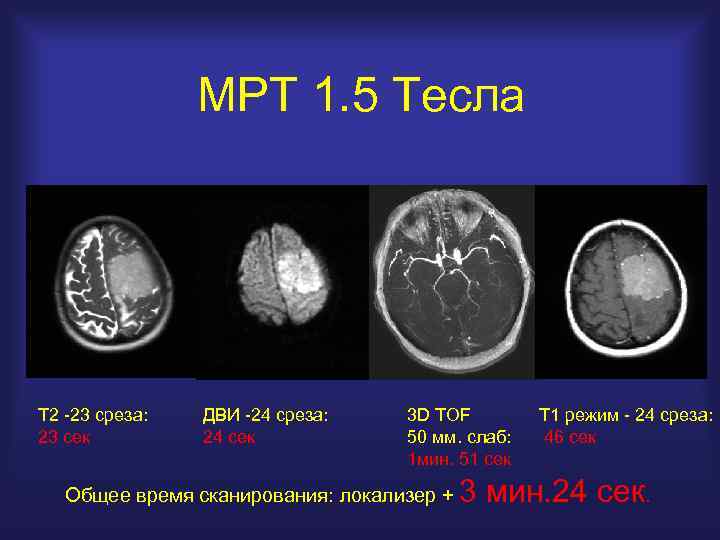

МРТ 1. 5 Тесла Т 2 -23 среза: 23 сек ДВИ -24 среза: 24 сек 3 D TOF 50 мм. слаб: 1 мин. 51 сек Общее время сканирования: локализер + Т 1 режим - 24 среза: 46 сек 3 мин. 24 сек.